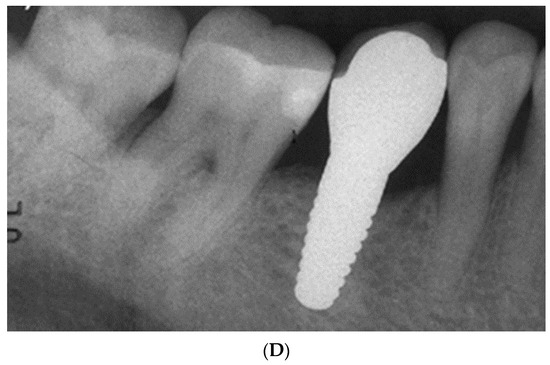

- Pirker, W.; Wiedemann, D.; Lidauer, A.; Kocher, A.A. Immediate, single stage, truly anatomic zirconia implant in lower molar replacement: A case report with 2.5 years follow-up. Int. J. Oral Maxillofac. Surg. 2011, 40, 212–216. [Google Scholar] [CrossRef]

- Pirker, W.; Kocher, A. Immediate, non-submerged, root-analogue zirconia implant in single tooth replacement. Int. J. Oral Maxillofac. Surg. 2008, 37, 293–295. [Google Scholar] [CrossRef]

- Pirker, W.; Kocher, A. Immediate, non-submerged, root-analogue zirconia implants placed into single-rooted extraction sockets: 2-year follow-up of a clinical study. Int. J. Oral Maxillofac. Surg. 2009, 38, 1127–1132. [Google Scholar] [CrossRef]

- Pessanha-Andrade, M.; Sordi, M.B.; Henriques, B.; Silva, F.S.; Teughels, W.; Souza, J.C.M. Custom-made root-analogue zirconia implants: A scoping review on mechanical and biological benefits. J. Biomed. Mater. Res. B Appl. Biomater. 2018, 106, 2888–2900. [Google Scholar] [CrossRef]

- Regish, K.M.; Sharma, D.; Prithviraj, D.R. An overview of immediate root analogue zirconia implants. J. Oral Implantol. 2013, 39, 225–233. [Google Scholar] [CrossRef] [PubMed]